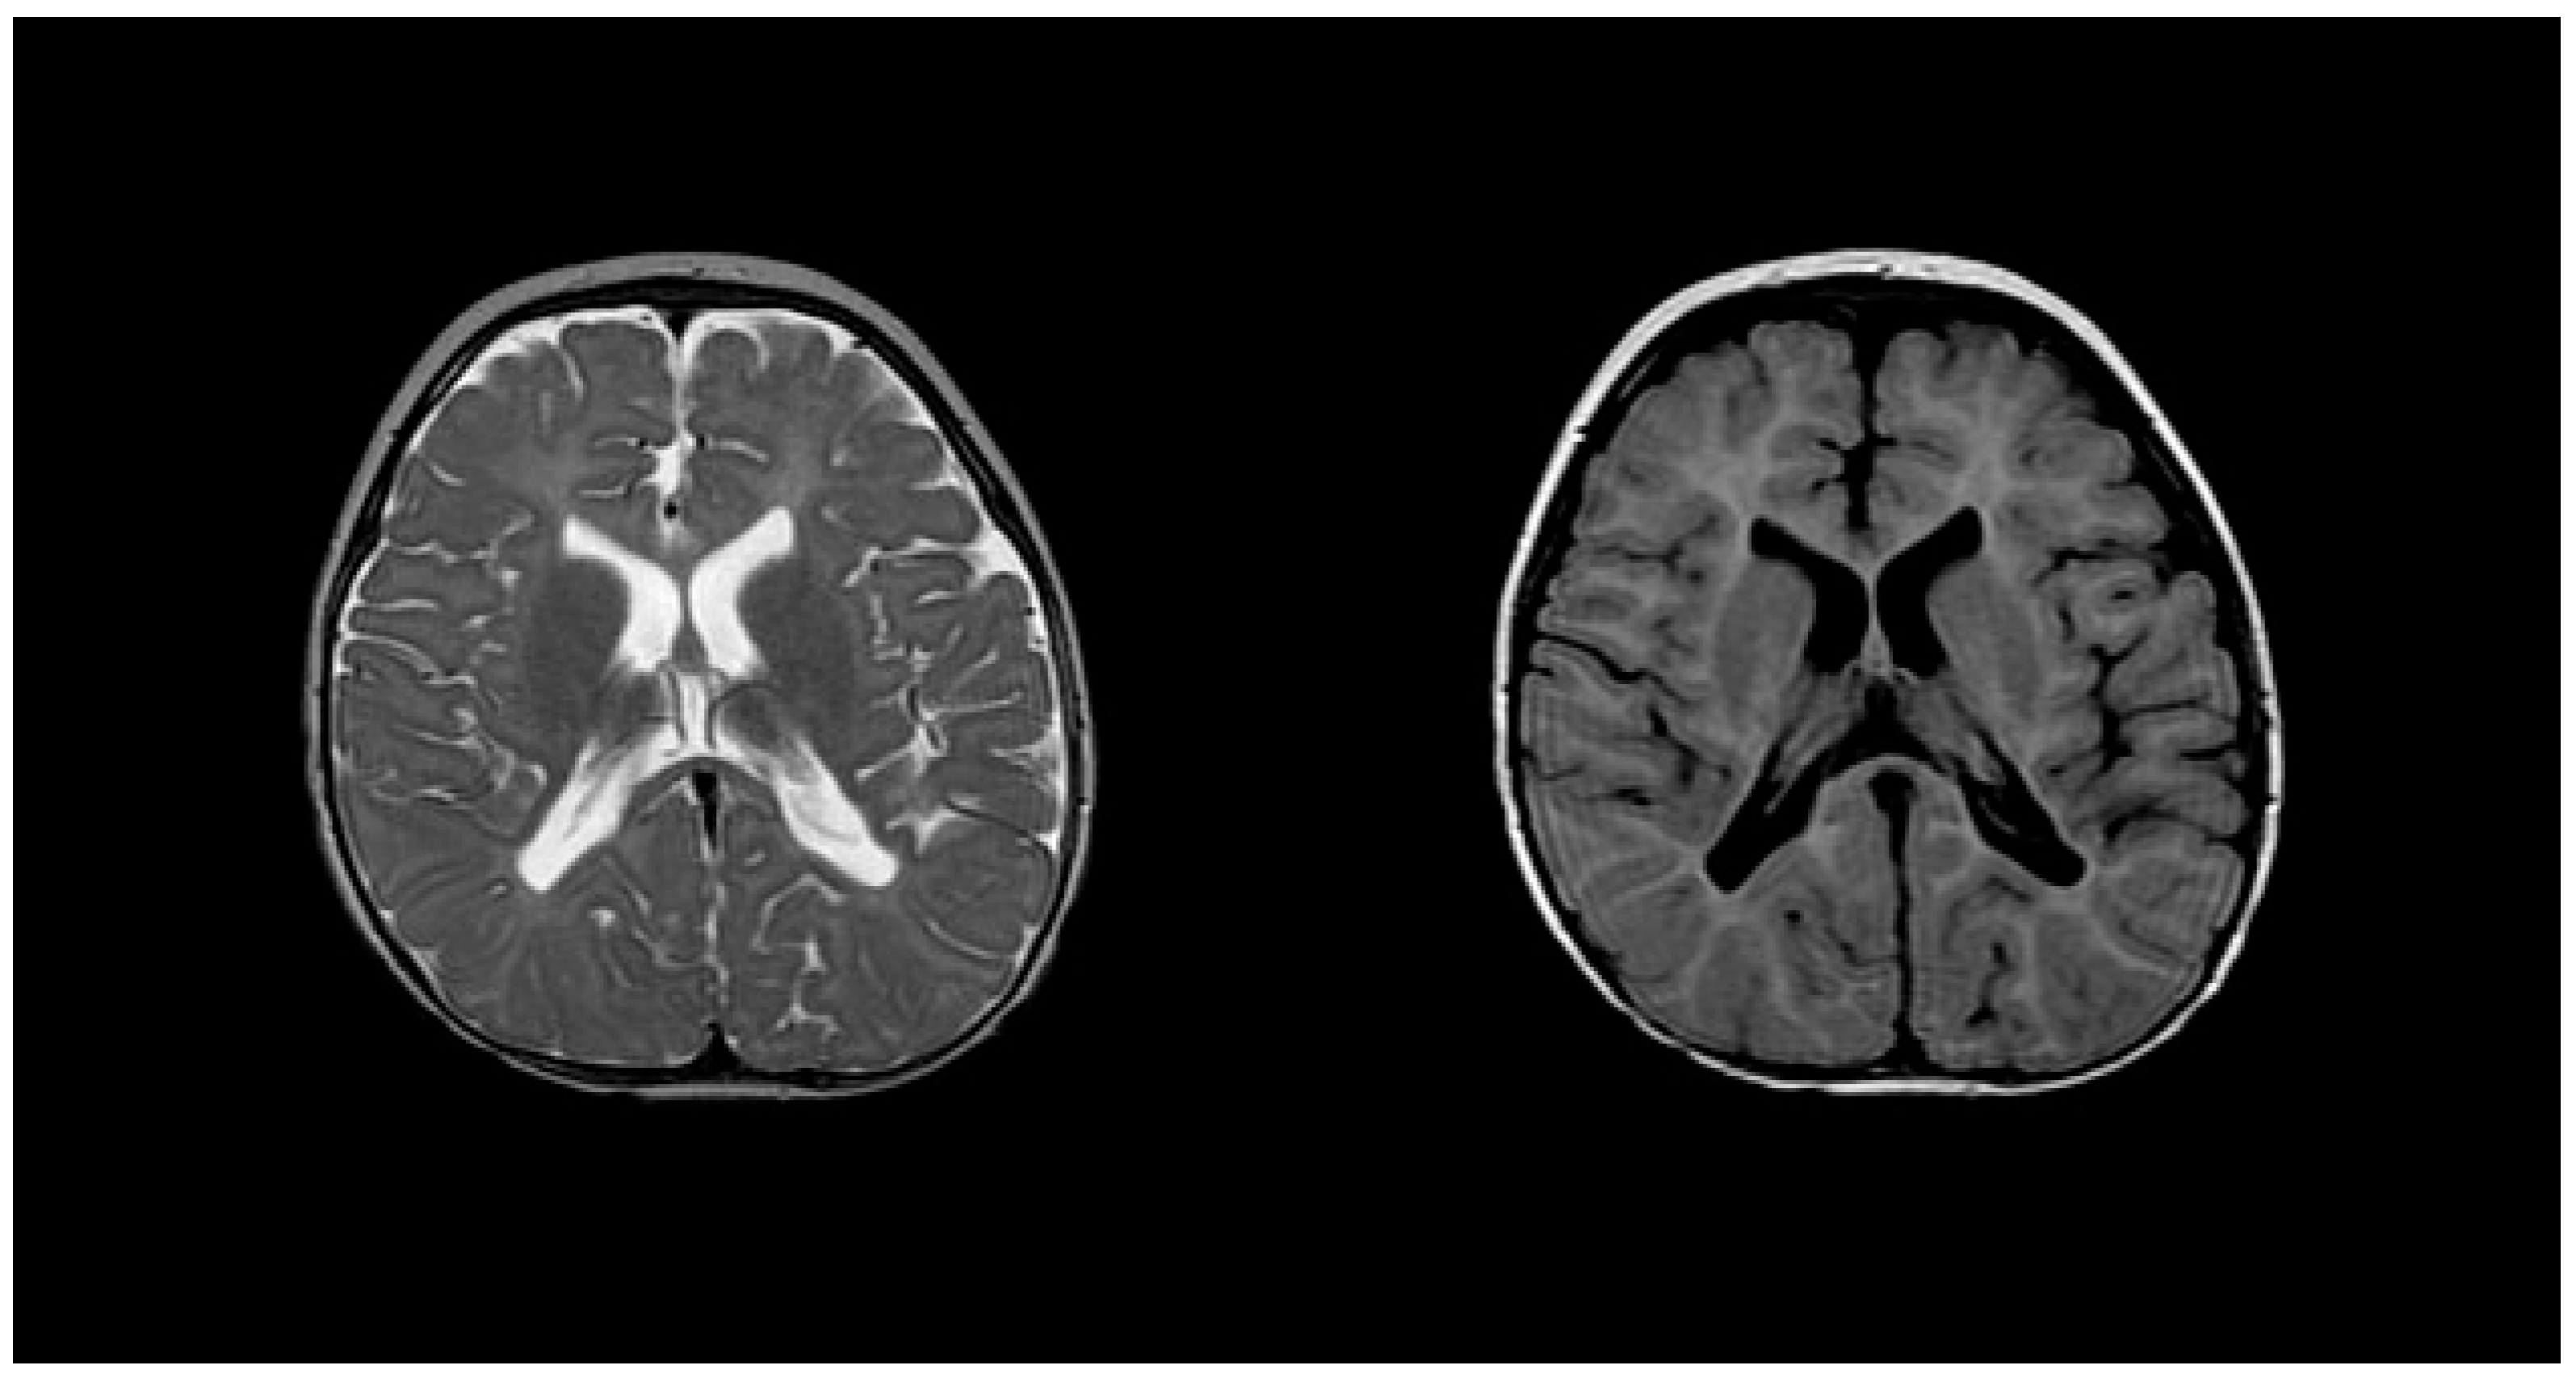

- Nezu, A.; Kimura, S.; Takeshita, S.; Osaka, H.; Kimura, K.; Inoue, K. An MRI and MRS study of Pelizaeus-Merzbacher disease. Pediatr. Neurol. 1998, 18, 334–337. [Google Scholar] [CrossRef]

- Sumida, K.; Inoue, K.; Takanashi, J.; Sasaki, M.; Watanabe, K.; Suzuki, M.; Kurahashi, H.; Omata, T.; Tanaka, M.; Yokochi, K.; et al. The magnetic resonance imaging spectrum of Pelizaeus-Merzbacher disease: A multicenter study of 19 patients. Brain Dev. 2016, 38, 571–580. [Google Scholar] [CrossRef]